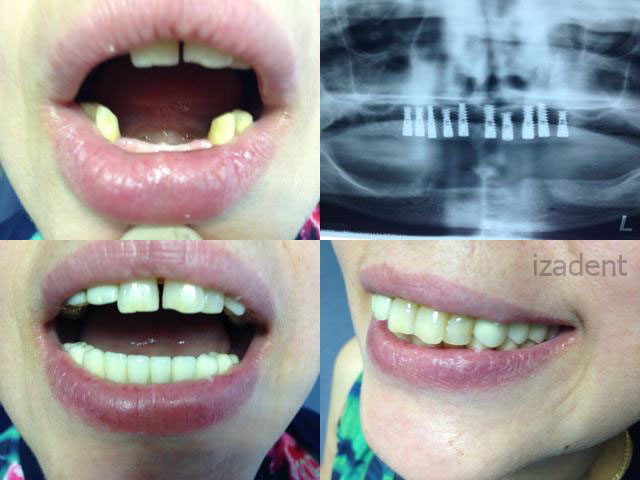

Cazul 2

Inainte

Dupa